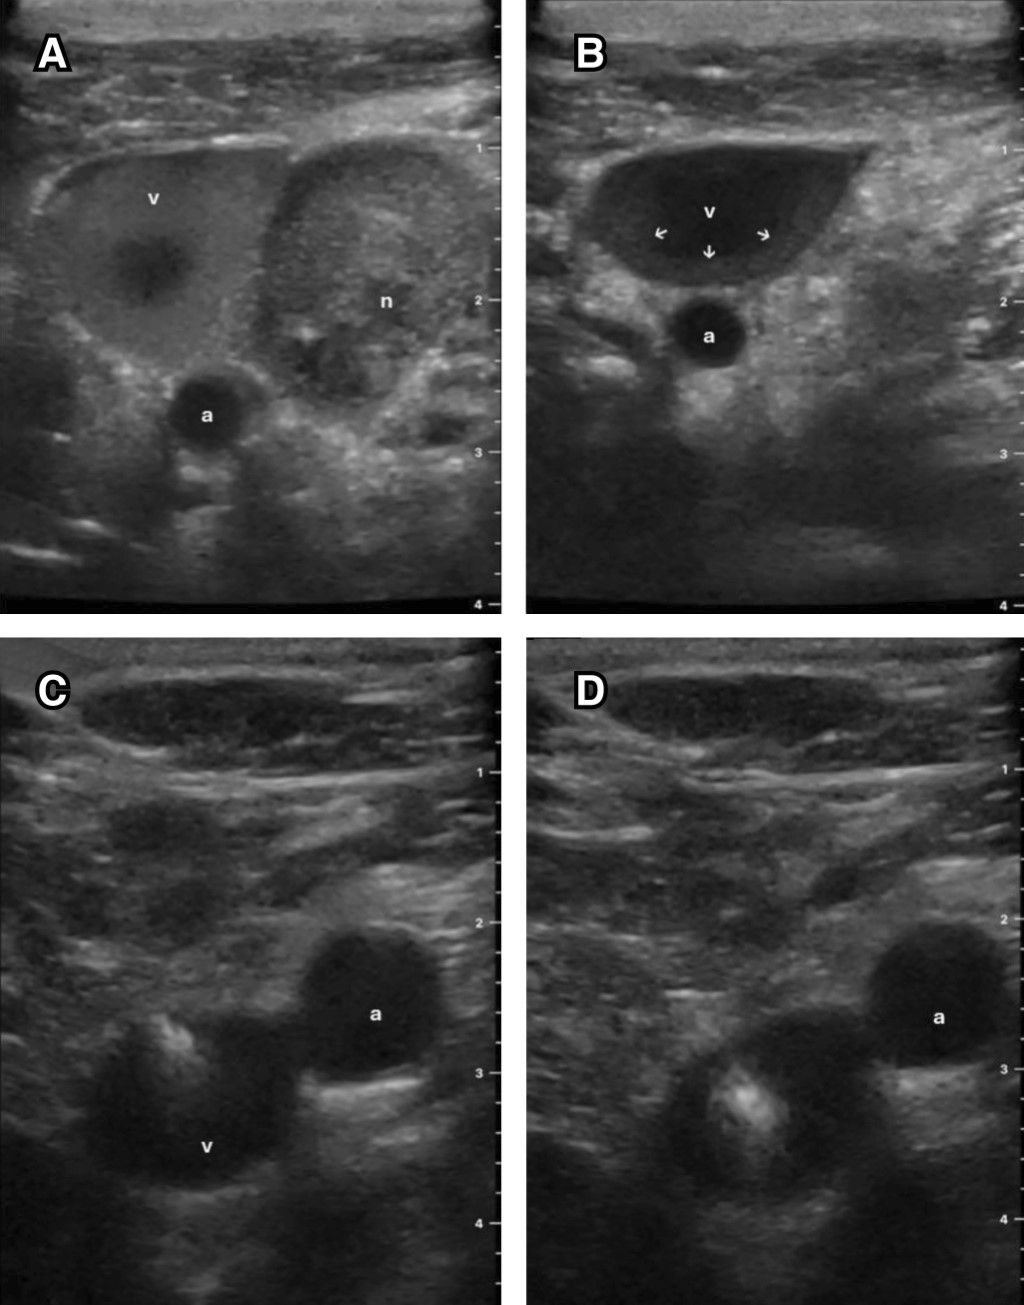

Por presentar inestabilidad hemodinámica, inician aminas vasoactivas vía periférica y posteriormente intentan la colocación de CVC en la región yugular y subclavia derecha en múltiples ocasiones. Logrando puncionar las venas y obtener retorno venoso, pero sin conseguir el paso de la guía metálica, con "acodamiento" de la misma. Se realizó rastreo vascular ecográfico con el que se observan múltiples adenopatías cervicales perivasculares, acompañadas de congestión venosa yugular y fenómeno de autocontraste (Figura 1). Se decide entonces colocar un CVC femoral izquierdo, por ser el mejor sitio disponible; se consigue al primer intento y sin complicaciones. Posteriormente, mediante tomografía axial computarizada (TAC) contrastada de tórax, se observó un gran tumor mediastinal y trombosis venosa asociada que ocasionaba síndrome de vena cava superior, lo cual no permitía el paso de la guía metálica.

Figura 1